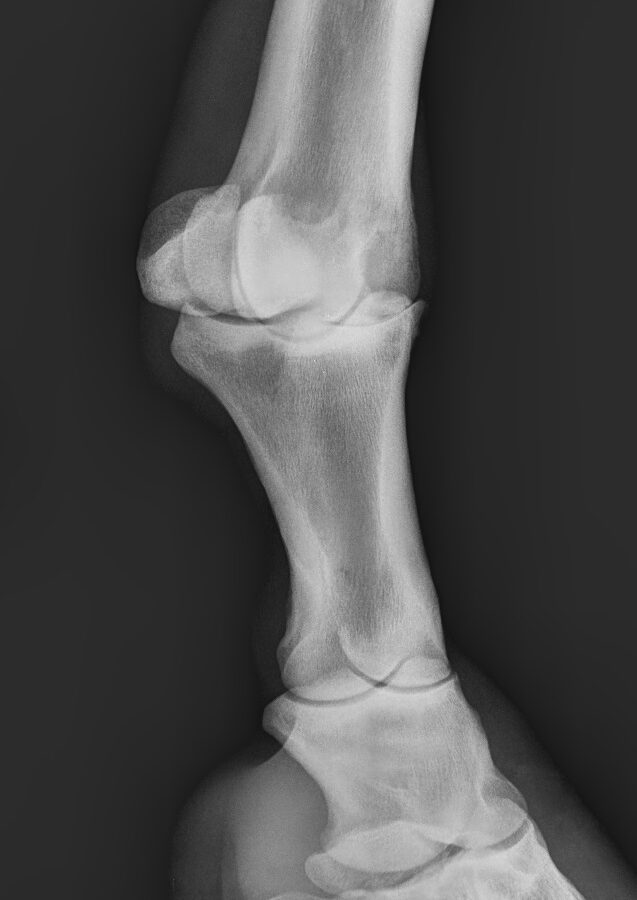

In any case it is difficult to determine the severity of a limp, it is very important that any indication or doubt about the condition of your horse and its joints is reviewed by a veterinarian specializing in equine sports medicine, having to perform different tests such as radiographic examination , Ultrasound examination, MRI, and / or arthroscopy.